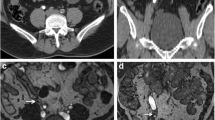

A 49-year-old male with right ureteropelvic junction obstruction. The visualization of dilated right renal calyces and pelvis are blurred due to respiratory artifacts in RT-FSE MRU (a MIP; c source image), whereas 3D BH-GRASE MRU (b MIP; d source image) displays them clearly (arrows). The acquisition times were 5 min 8 s for 3D RT-FSE MRU and 14.8 s for 3D BH-GRASE MRU